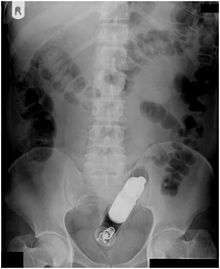

Rectal foreign bodies are large foreign items found in the rectum that can be assumed to have been inserted through the anus, rather than reaching the rectum via the mouth and gastrointestinal tract. Smaller, ingested foreign bodies, such as bones eaten with food, can sometimes be found stuck in the rectum upon x-ray.